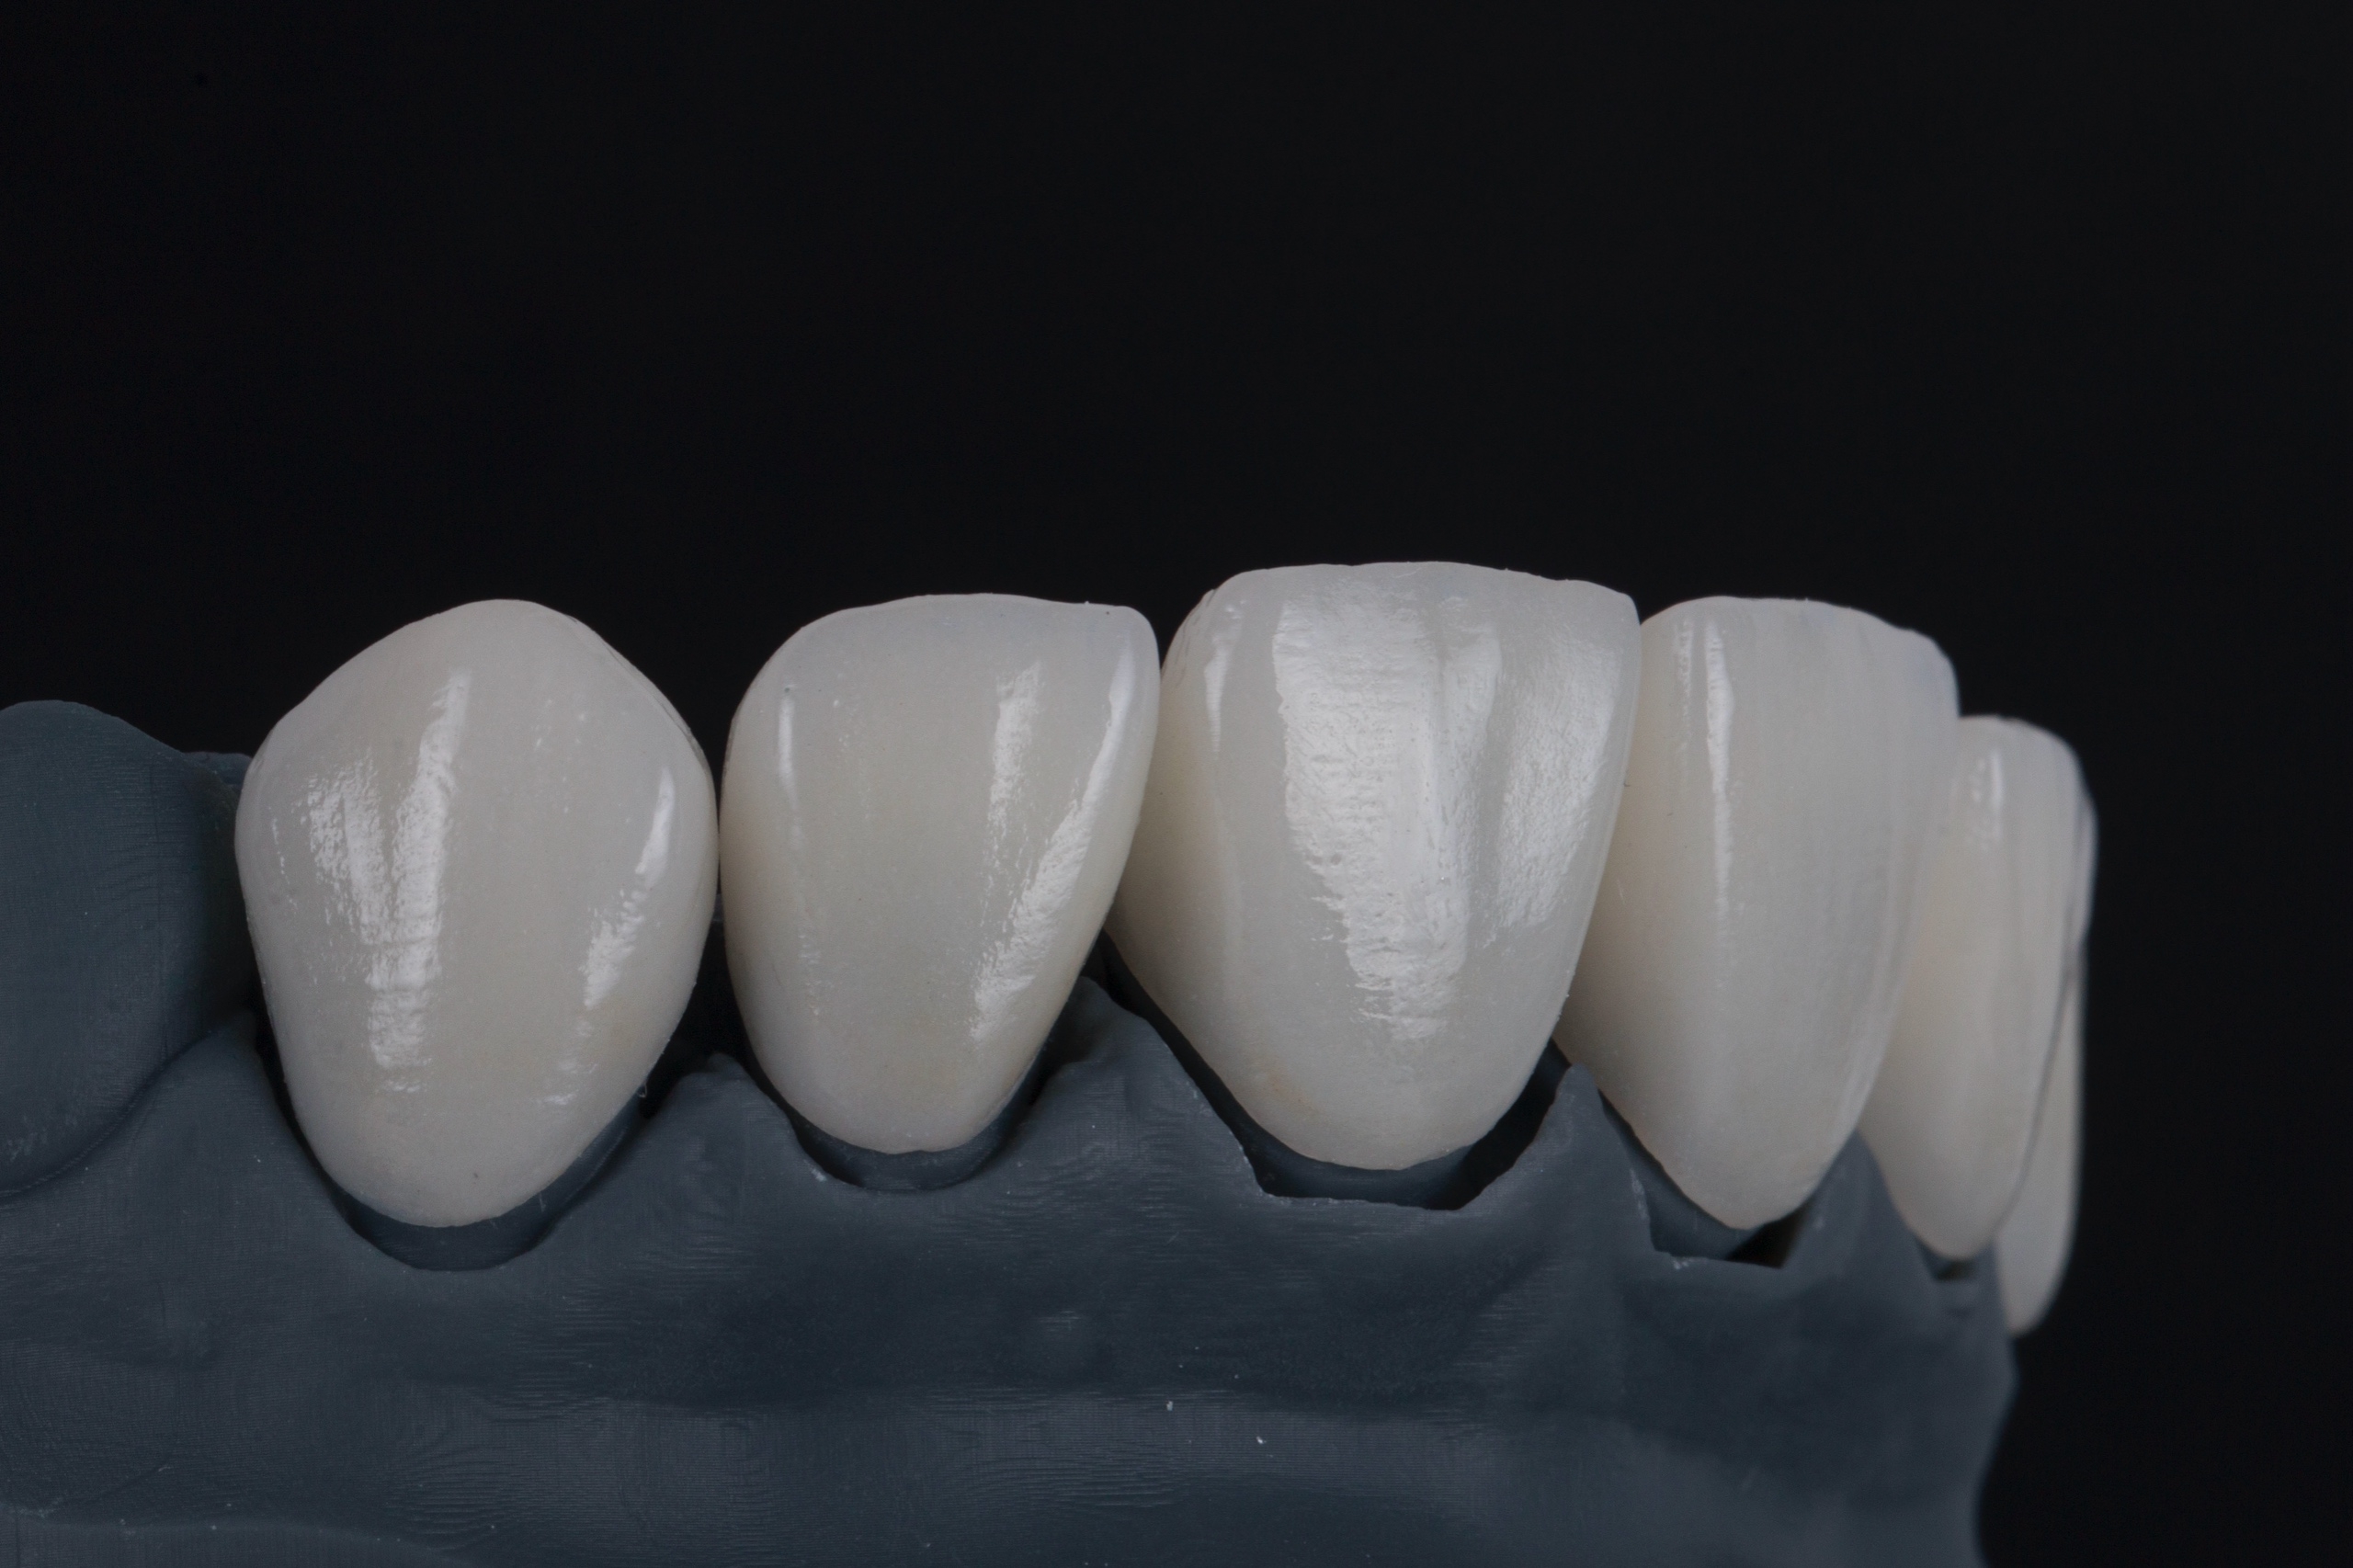

Виниры

От 33 500 Виниры фото